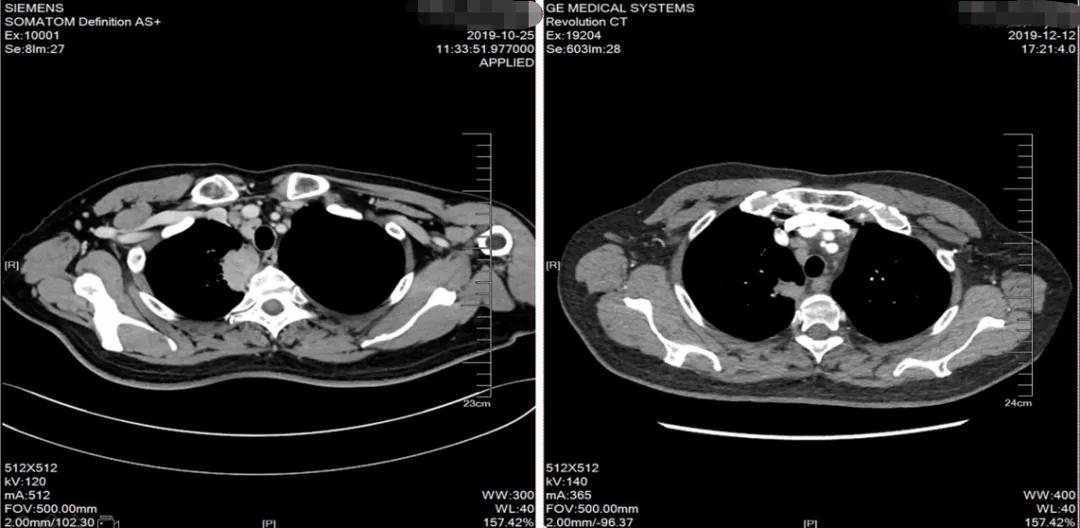

2019-10因无明显诱因下发热,于当地医院就诊,胸部CT提示:右上肺占位(5.6*4.8cm)。 考虑肺癌,伴纵膈淋巴结多发转移。

2019-10-25于广医一院行PET/CT检查考虑右上肺肺癌并右肺门、纵隔淋巴结转移。头颅MR:右侧额叶异常信号影, 考虑转移瘤。 双侧额顶叶散在缺血灶。

2019-10-25 PET/CT示右上肺癌伴纵膈多发淋巴结转移

2019-12-12胸部CT示考虑右上肺癌并右肺门及纵隔淋巴结转移,较前缩小